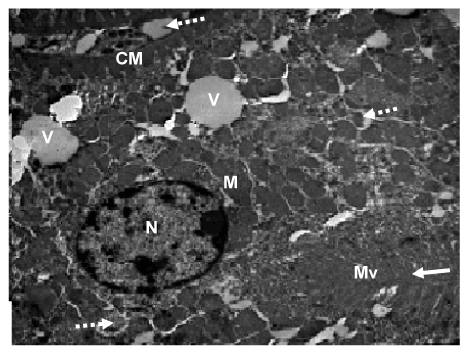

| Figure 22: Ultramicrograph of a section of kidney of rat exposed to Cd Cl2 for 8 weeks, showing cell of proximal convoluted tubule with rounded heterochromatic nucleus (N), basal elongated mitochondria (M), and thick enfolded cell membrane (CM) .disorganized apical microvilli (Mc) around the tubular lumen (arrow). The protoplasm appeared to be contains numerous vacuoles (V) and lysosomes (broken arrows). TEM mag. =8000X. |